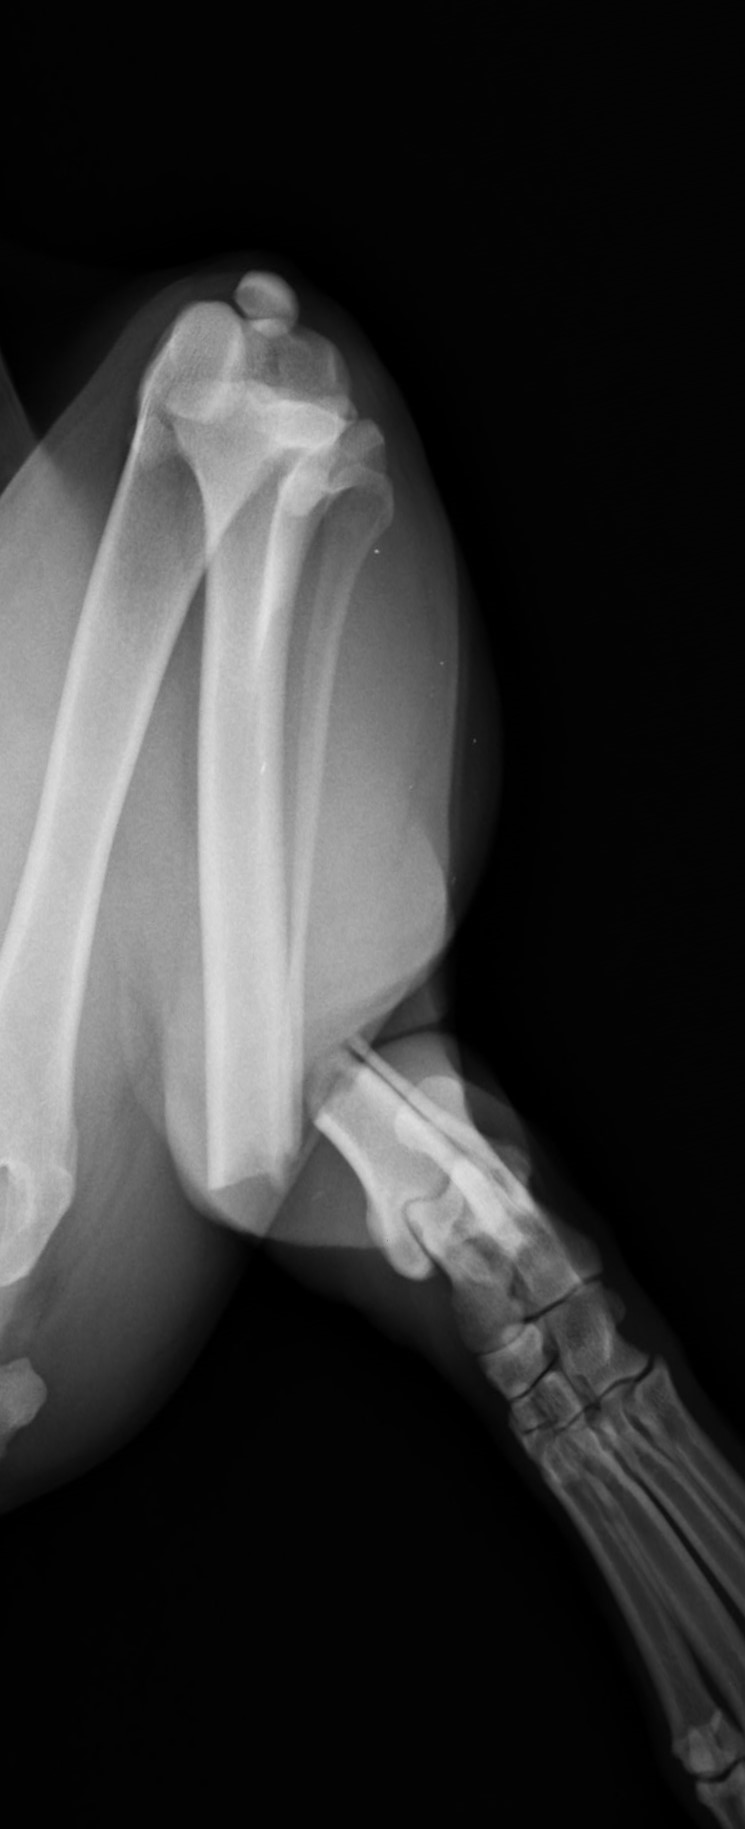

5~6歳以上の去勢手術をしていないオス犬に多い病気ですが、メス犬や去勢した犬に起こることもあります。お尻の筋肉が萎縮した結果、筋肉の隙間から直腸や膀胱が皮膚の下にとびでてしまいます。これにより便が出にくくなったり膀胱炎になったりします。手術をすることで機能回復および今後の致死的な状況を回避することができます。当院では去勢手術→結腸固定→前立腺固定→骨盤隔膜構成筋の縫縮→内閉鎖筋フラップ→浅臀筋フラップの順で通常腹側・臀部左右両側同時に行います。また老化以外に、筋肉が萎縮する原因があったり、腹圧がかかる原因があったりする場合も多いので、再発防止のためそれらの診断・治療も重要です。今回のワンちゃんも無事手術も終わり元気に退院しました。よかったね。